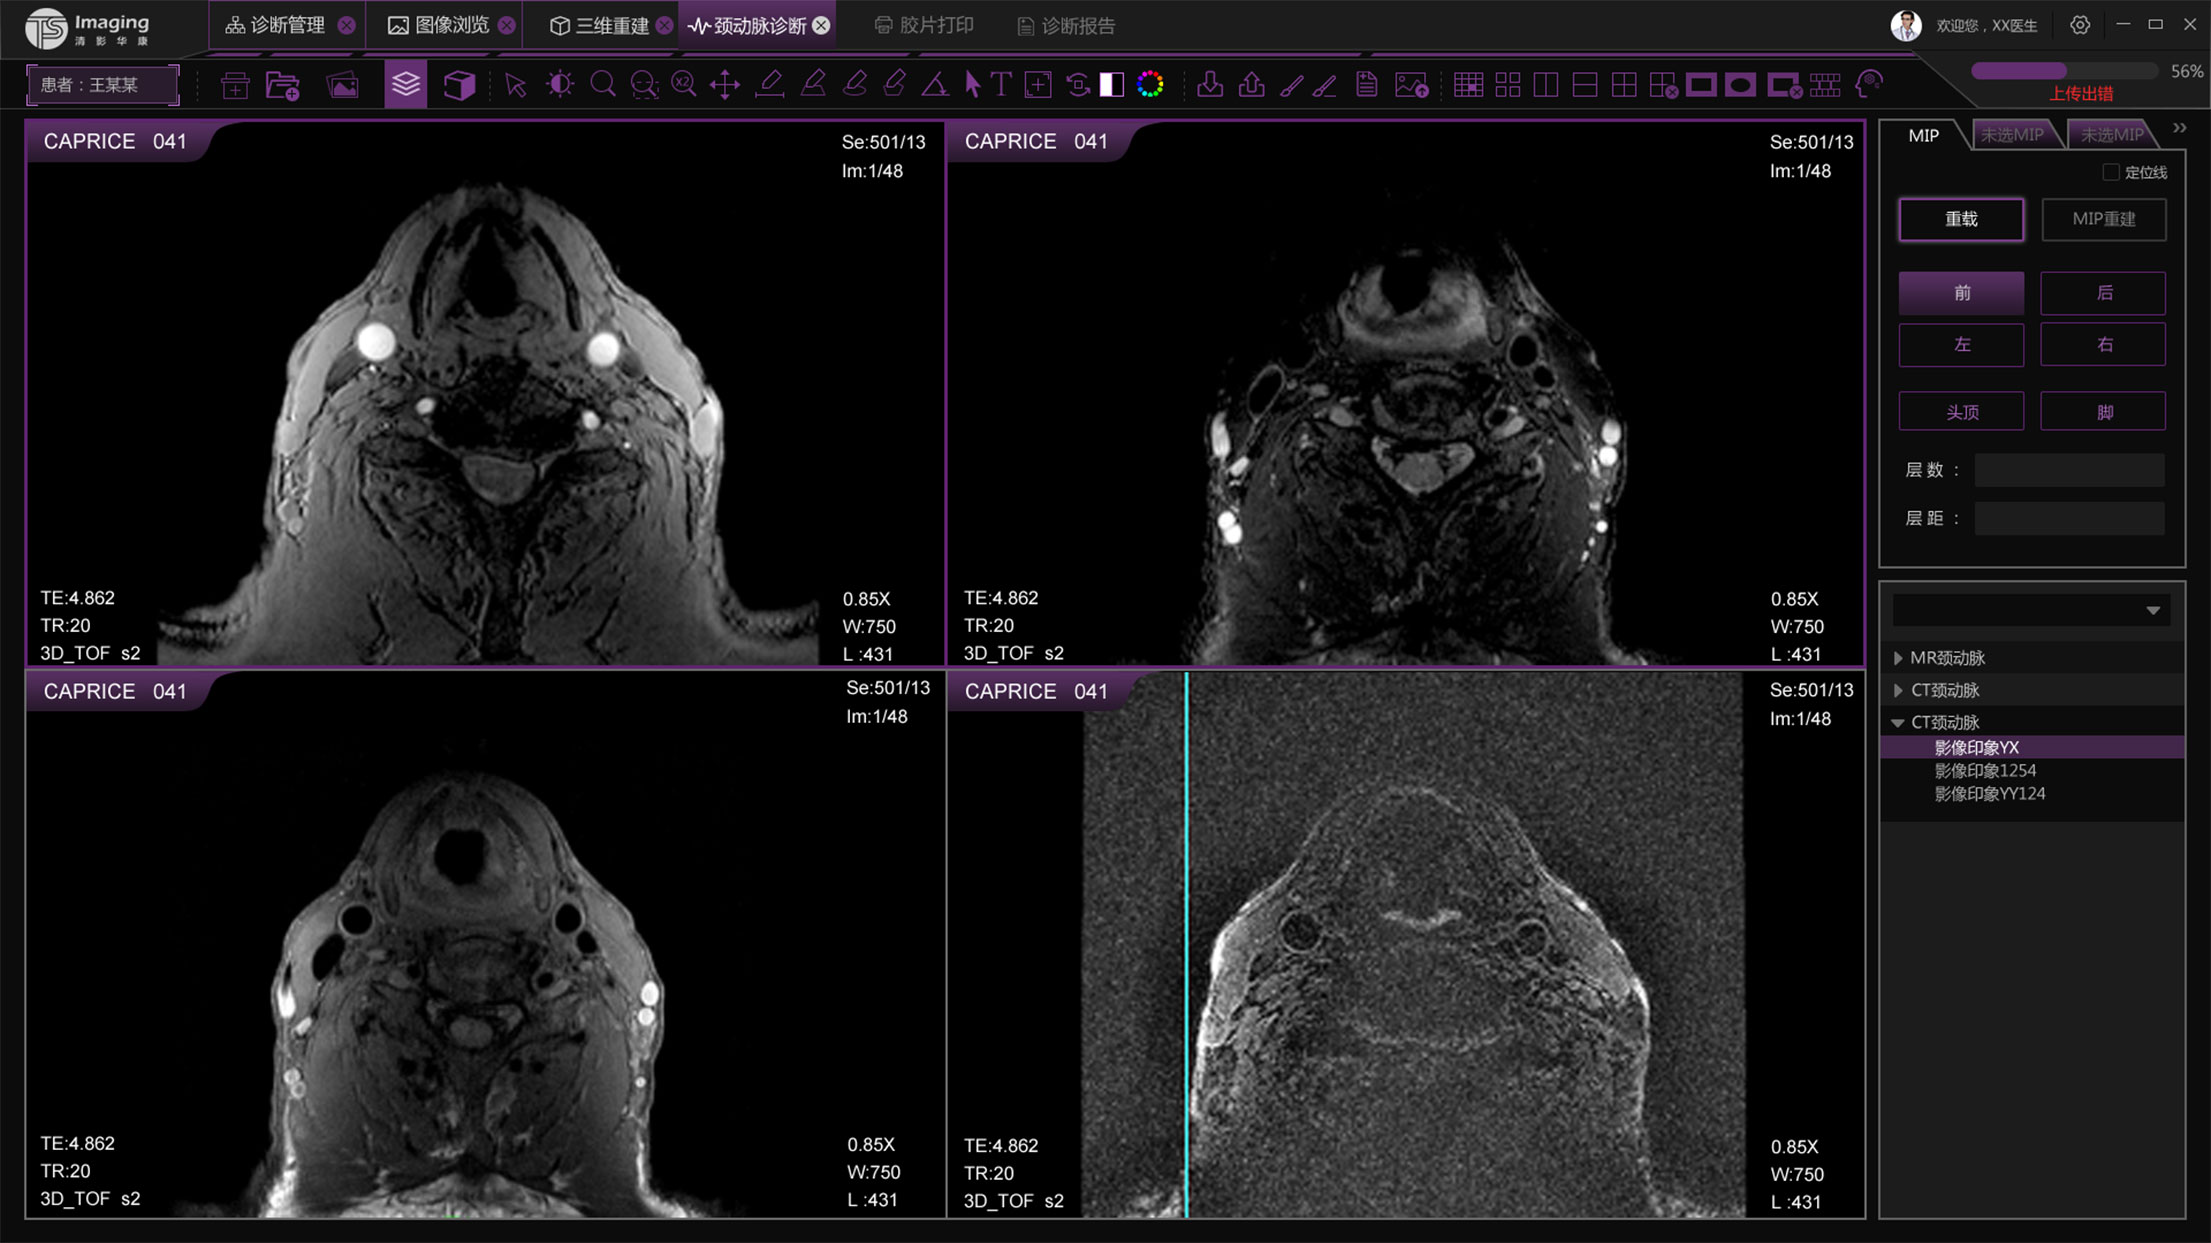

頸動(dòng)脈診斷頁面

頸動(dòng)脈診斷頁面整體布局和三維重建比較相似,最大的區(qū)別是右側(cè)的操作區(qū)域,血管分析都為按鍵操作,通過間隔的大小分成三部分。單層切片除了按鍵還有下拉菜單的操作。